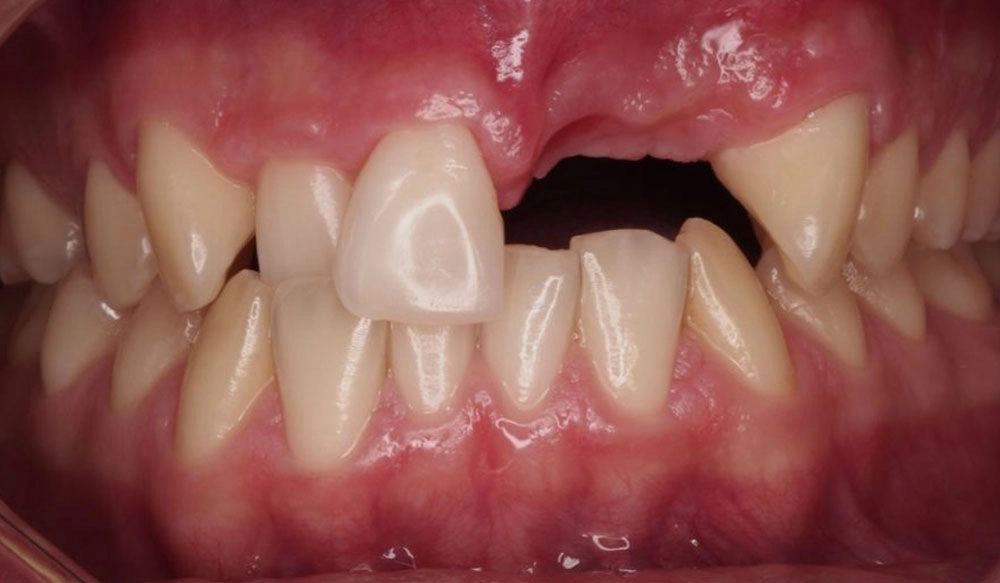

Điều trị giai đoạn 1

Điều trị sớm cho bệnh nhân trẻ (6-10 tuổi): Điều trị sớm có thể mang lại lợi ích tốt nhất cho bệnh nhân nếu vấn đề của trẻ có thể trở nên nghiêm trọng hơn theo thời gian nếu không được điều trị. - Ngăn chặn vấn đề đang phát triển; Loại bỏ nguyên nhân; Điều hướng sự phát triển của xương mặt và xương hàm; Cung cấp đủ không gian cho răng vĩnh viễn mọc.

Thông tin bệnh nhân:

Tuổi: 9

Giới tính: Nam

Lựa chọn điều trị Invisalign: Invisalign cho thanh thiếu niên với MA

Tổng thời gian điều trị:

13 tháng